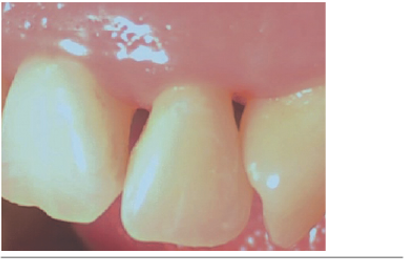

Paciente sexo femenino de 23 años de edad, sin antecedentes mórbidos relevantes y tratada periodontalmente. Presenta defectos de triángulo negro en papilas gingivales del sector anterior del maxilar superior (Figuras 1 y 2).

Las papilas fueron clasificadas según la clasificación de Norland y Tarnow1, dando los siguientes resultados. La papila entre los dientes 1.3 - 1.2 clase III, papila entre 1.2 - 1.1 clase II (Figura 1), papila entre 1.1 - 2.1 clase I, papila entre 2.1 - 2.2 clase I (Figura 2) y papila entre 2.2 - 2.3 clase II.